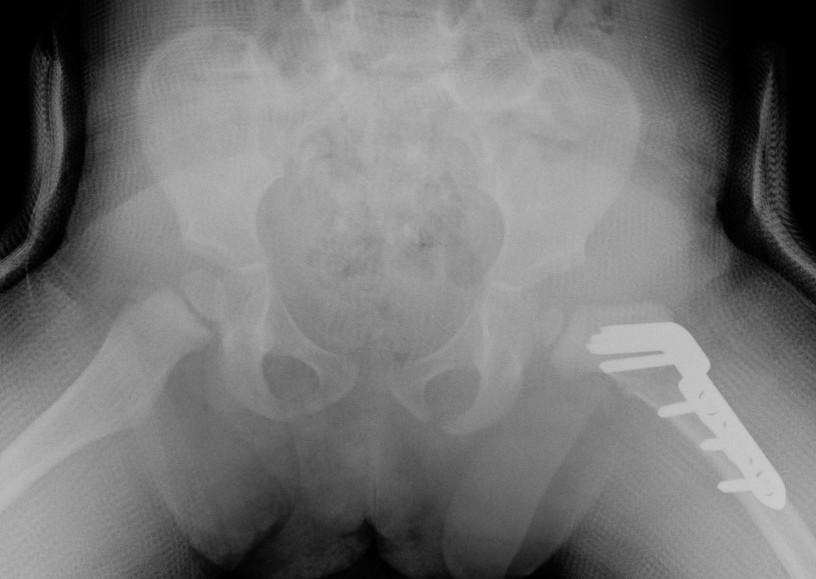

Xray

Dislocated hips in the setting of DDH with ncreased acetabular index